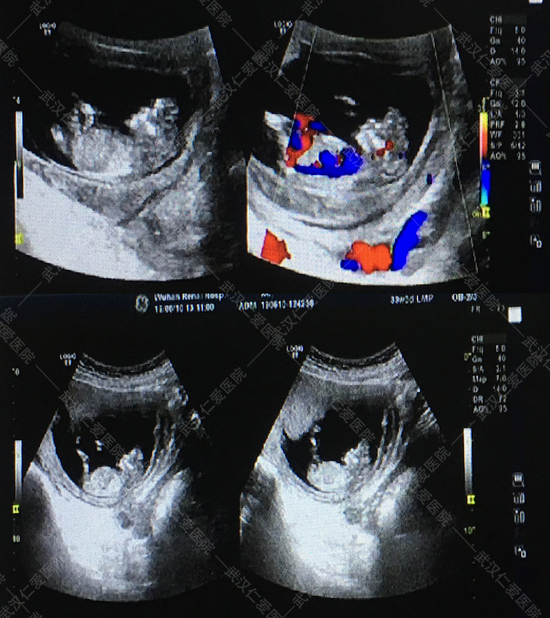

6月16号,武汉仁爱医院NT筛查出两例畸形胎儿,一例多器官多系统畸形,一例露脑畸形,这两位孕妈都是孕12周+,其中一位还是高龄产妇今年33岁,喜怀二胎,本来是高高兴兴的来做产检,没想到NT筛查出胎儿露脑畸形。

露脑畸形

对于NT检查,很多孕妈不是很了解,认为和普通B超差不多,甚至还有一些孕妈觉得NT筛查可做可不做。武汉仁爱医院超声影像科王娟主任解释:“NT筛查主要是通过B超检查胎儿颈部透明层较厚的部位,用于早期诊断胎儿是否存在唐氏综合征等染色体疾病及其他发育异常,很多孕妈没等做四维彩超就被确诊畸形的,所以这项检查不容忽视。”

NT检查对医生专业度要求较高,所以孕妈妈们一定要到正规的医院做检查,武汉仁爱医院在NT检查上应用超声影像技术,为检查和诊断获得清晰的图像,检查结果更精准,让孕妈妈们更安心。